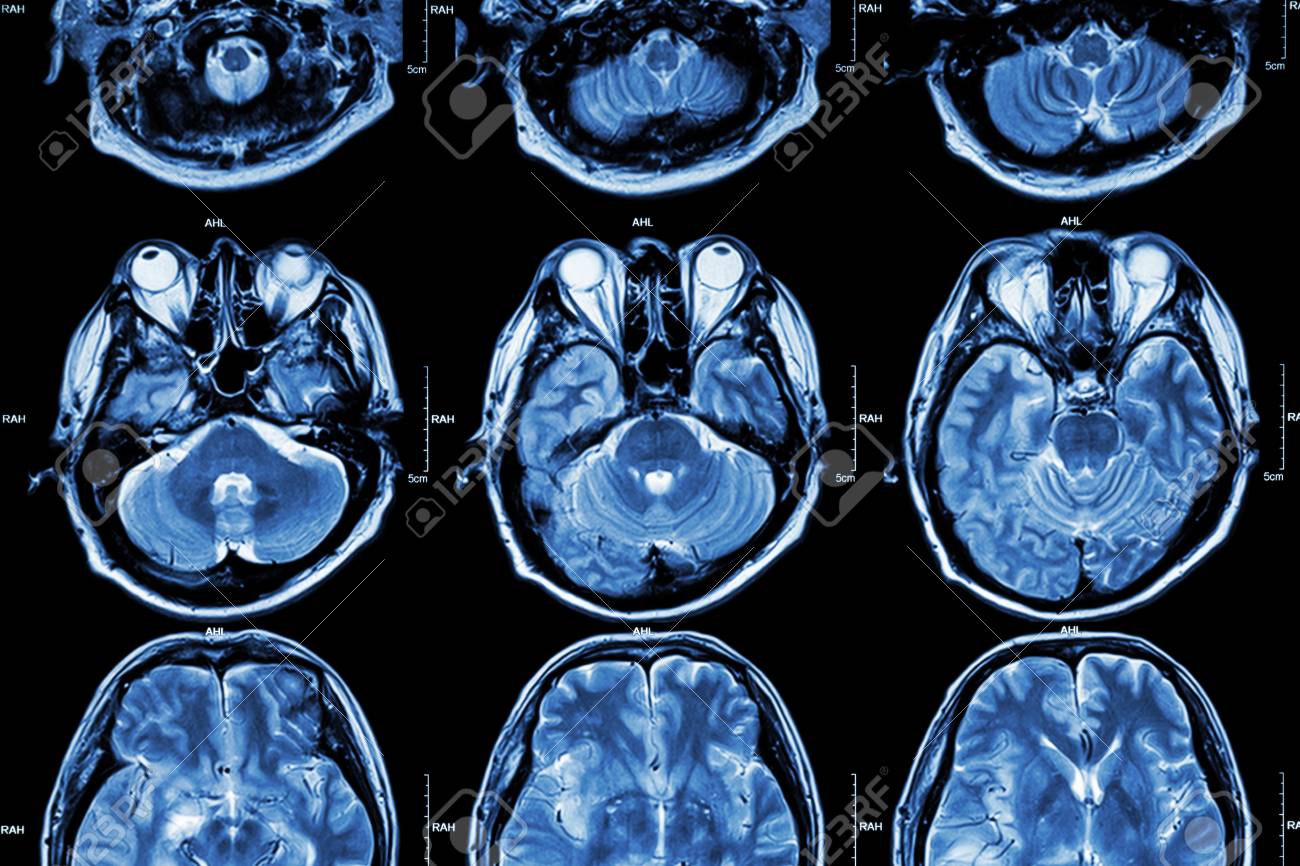

検査結果

精密検査をしたら脳に大きめの悪性腫瘍があったプー